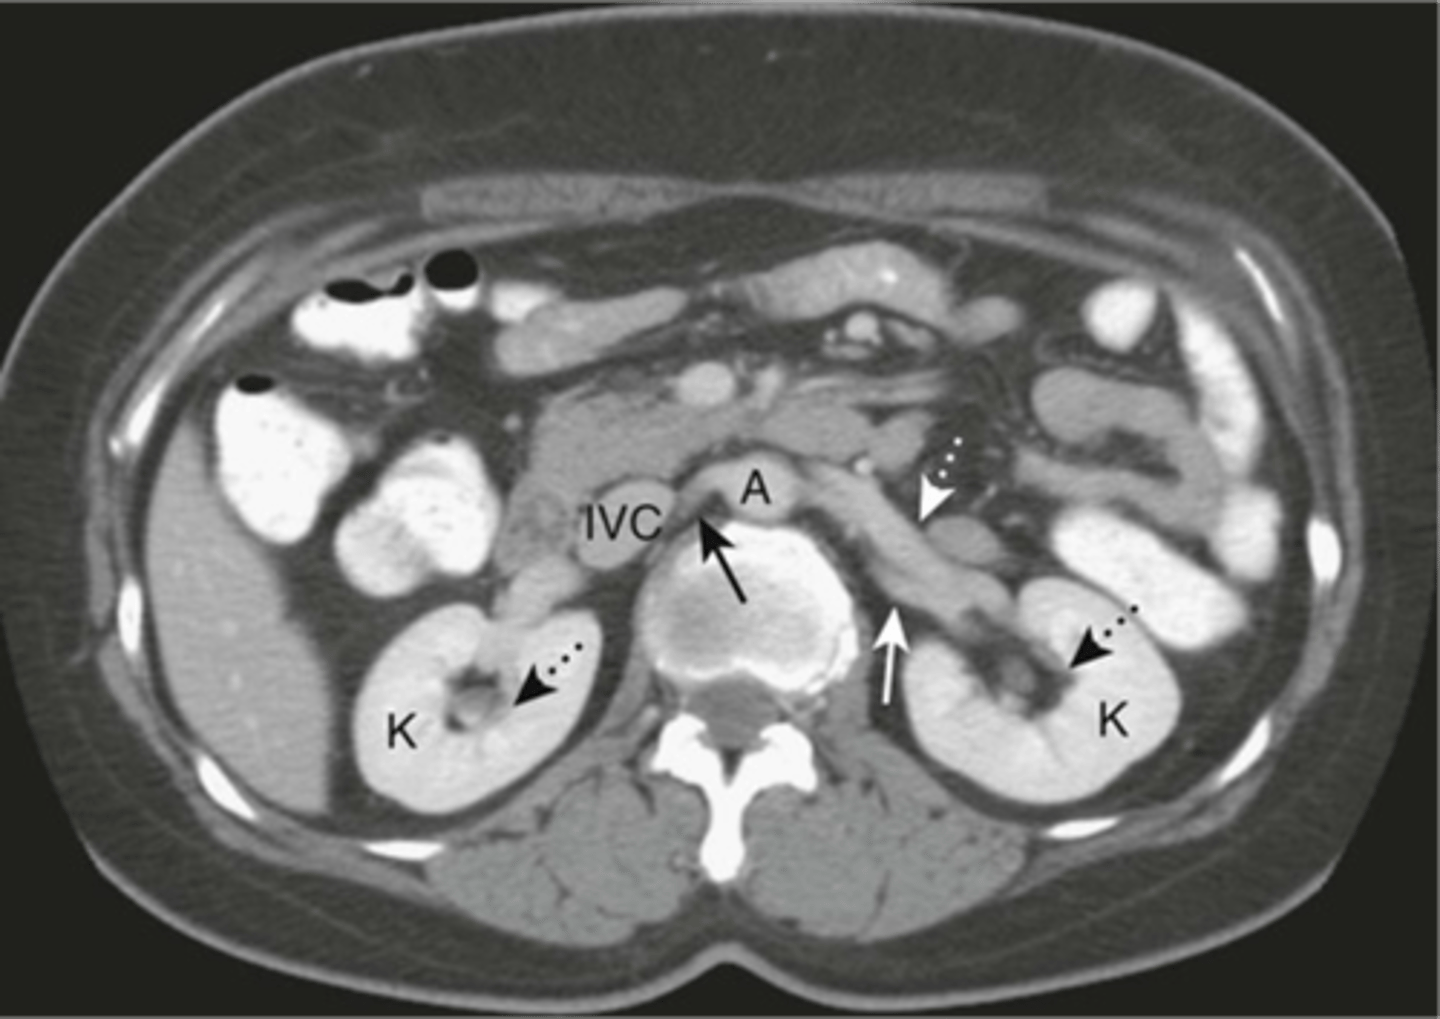

Normal anatomy in axial CT

Normal CT